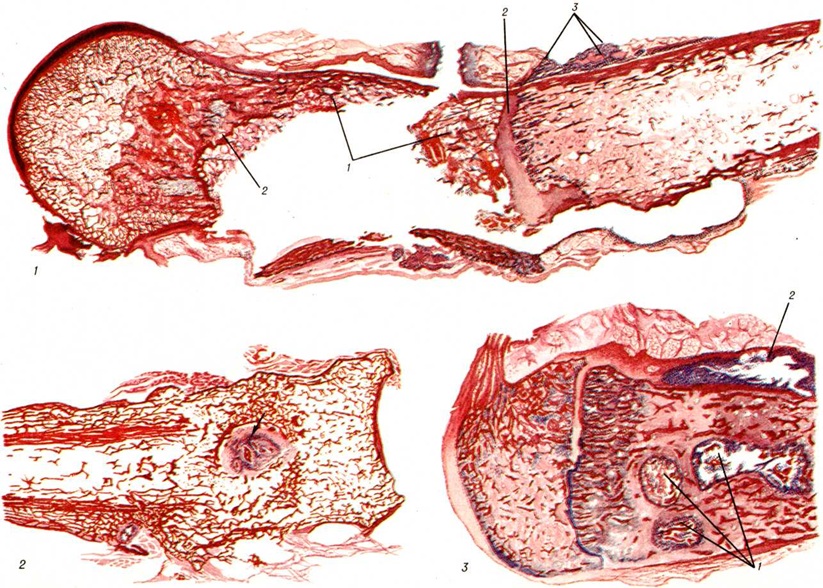

В других случаях наблюдается инкапсуляция гнойников в кости. К 3—4-й недель от начала заболевания при рентгенологическое исследовании на фоне рарефикации определяются очаги некроза кости, поскольку омертвевшая кость не подвергается резорбции и сохраняет прежнюю плотность. При патологоанатомическом исследовании участки некроза выявляются ещё раньше. В дальнейшем те из них, которые находятся в самом очаге нагноения, подвергаются секвестрации (рисунок 1). Секвестрация (смотри полный свод знаний Секвестр, секвестрация) заключается в отторжении омертвевших участков кости, находящихся в полости гнойника, от окружающей костной ткани. При этом в случае образования секвестра в компактной пластинке на её поверхности в зоне прилегания грануляций возникает и постепенно углубляется секвестральная борозда, а в толще — расширение гаверсовых каналов и слияние их между собой. После того как все костное вещество в указанной зоне растворится, секвестр оказывается свободно лежащим в полости гнойника (цветной рисунок 2 и 3). Секвестры губчатого вещества кости отделяются от остальной её части за счёт растворения прилежащих костных балок, находящихся в зоне грануляций (рисунок 2).

Воспаление начинается в мягких тканях краёв раны в виде диффузной воспалительной инфильтрации, вслед за которой на границе с зоной омертвения формируется демаркационная линия. Одновременно образуется экссудат, поступающий в полость раны и пропитывающий некротизированные ткани, подвергающиеся при этом расплавлению, а часто и гнилостному распаду. К 4— 5-му дню в зоне демаркационной линии образуются грануляции, обильно продуцирующие гной. К этому сроку проявляется и гнойное воспаление в отломках кости, которое протекает на границе с некротизированными тканями, сохраняя характер демаркационного. С началом нагноения омертвению могут подвергнуться связанные с периостом костные осколки и мягкие ткани, испытавшие коммоцию — зона резерва некроза по И. В. Давыдовскому. Очаг нагноения постепенно изолируется валом из грануляций, а в последующем и соединительнотканной капсулой. В нем располагаются свободные костные осколки, не удалённые при хирургической обработке раны, осколки, сохранившие связь с периостом, концы отломков, лишённые периоста, инородные тела, обрывки мягких тканей, распадающиеся кровяные свёртки (рисунок 3). Нагноение нередко распространяется в глубь мягких тканей и в толщу кости вдоль трещин и каналов, проделанных сместившимися в момент ранения костными осколками, что придаёт очагу сложные очертания (цветной рисунок 1).

В ходе нагноения происходит расплавление омертвевших тканей под действием ферментов гноя и выделение их из раны, а также секвестрация омертвевших участков кости, находящихся в очаге нагноения. Темпы секвестрации снижаются при обширном параоссальном нагноении, задержке гноя в ране, тяжёлой интоксикации.

В ходе нагноения в окружающих очаг тканях развёртываются пролиферативные и дистрофические процессы. В результате пролиферации тканей возникает гноеродная оболочка, а затем формируется костная мозоль (смотри полный свод знаний) с последующей консолидацией перелома или образуются лишь костные разрастания по краям отломков (рисунок 4). Возникшая костная мозоль включает в себя гнойники с секвестрами (цветной рисунок 2) и играет т. о. роль секвестральной капсулы, из которой свищевые ходы ведут на поверхность кожи (рисунок 5). Дистрофические изменения выражаются в диффузной рарефикации, а позже в очаговой эбурнеации кости (смотри полный свод знаний) в зоне образования мозоли. В окружающих мягких тканях и в соседних суставах развиваются явления атрофии.